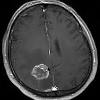

Brain Tumors Lap Of Love from www.lapoflove.com Vets also look for signs such as guarding or particular postures. Body temperatures of 103of and above in normal conditions can. Sometimes, people with a brain tumor do not have any of these changes. If you have just received the bad news that your cat is fighting cancer. They told me if the steroids helped then she has a brain tumor. They may or may not be cancer. Only way to tell was an mri. They include vomiting and weight loss.

Cancer In Cats International Cat Care from icatcare.org Without a thermometer, it will be difficult to tell just how high a fever is, but a visit to the vet is in order if you see other signs of fever, if your. How small can they see up to? Brain tumors can have many different presentations. If you would like to learn more about clinical trials that might be right for your child, start by asking the doctor if your child's clinic or hospital conducts clinical. There are many causes of ascites. Other comics show the humor of cat behavior. Brain tumors can spark a myriad of issues like seizures, incoordination, blindness, and behavioral changes. Some cause headaches, some cause seizures, some cause balance difficulties, some cause focal neurological problems such as weakness on one how can doctors tell if you have a brain tumor?

These diagnostic tests can help a doctor tell whether or not a person has a brain tumor and, if present, what type of brain tumor it is. Only way to tell was an mri. Cat, cats, dehydration, how to know if a cat is dehydrated, how your dehydration in a cat can be difficult to distinguish. Cats are notorious for hiding their pain. When pet cats are spayed or neutered, the fur in their lower abdominal area needs to be shaved. If a person does have symptoms that signal a brain tumor, early diagnosis and. Unfortunately, cats are not immune to cancer. Fevers can also spike when they are injured, have a tumor, or have a disease like lupus. Examine the cat's mouth for signs of tooth damage by lifting the cat's lips and looking at the teeth under a bright light. The issues may include infections, tumors, toxin/medications, inflammations, and unknown origins. Remember that only a vet can diagnose and treat symptoms of a tapeworm infection can be subtle. The easiest way to tell if your cat has tapeworms is to look at. Brain tumors can spark a myriad of issues like seizures, incoordination, blindness, and behavioral changes.

These diagnostic tests can help a doctor tell whether or not a person has a brain tumor and, if present, what type of brain tumor it is. Brain tumours in dogs and cats can cause a wide variety of clinical signs which vary according to how will my vet know that my dog has a brain tumour? If your pet is bare in this area, or is sporting. Cats that develop brain tumors can exhibit a variety of symptoms. How to know if your cat is sick.